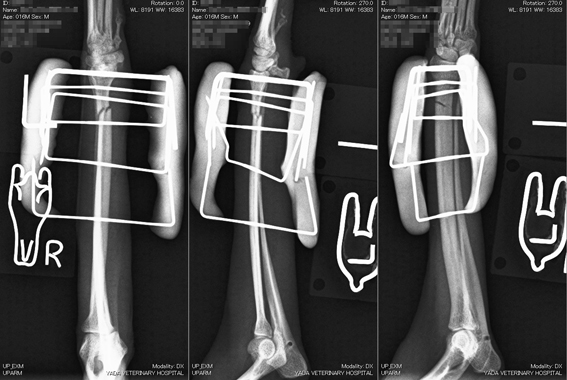

写真(上):手術中のX線写真

手術は、患部を切開することなく実施しています。(完全非開創手術)

創外固定ピンを刺入する部位の皮膚にレーザーで小さな穴を開けるだけで、骨折部を切開することなく整復固定が可能です。患者の負担は、軽くなります。

手術翌日には退院し、一週間以内に患肢をつかって走ることもできるようになります。

写真中段: 手術直後

写真下段: 抜ピン後

手術後1ヶ月半で抜ピンしました。

骨に黒く写る線は、ピンの入っていた痕です。